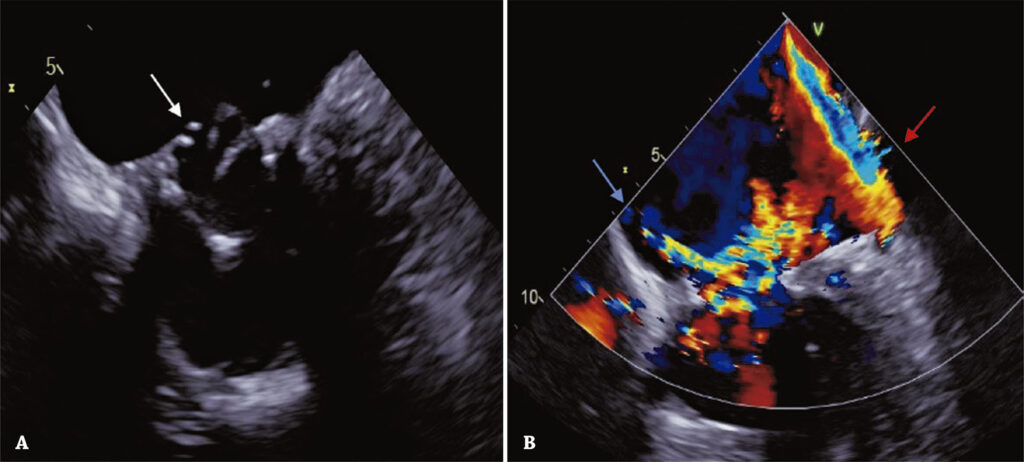

A substituição transcateter valve-in-valve da valva mitral surgiu recentemente como uma alternativa cada vez mais utilizada nos pacientes de alto risco cirúrgico. O presente caso relata uma substituição de valva mitral transcateter valve-in-valve, por via transeptal, como tratamento da degeneração de uma bioprótese mitral cirúrgica e regurgitação grave, em paciente de 86 anos já submetido a uma substituição transcateter valve-in-valve aórtica, há 6 anos. Este caso enfatiza o papel crucial de uma avaliação pré-operatória cuidadosa, com uso de diferentes modalidades de exames de imagem, para planejamento do procedimento, em paciente com maior risco de obstrução da via de saída do ventrículo esquerdo, devido a um procedimento valve-in-valve aórtico prévio.